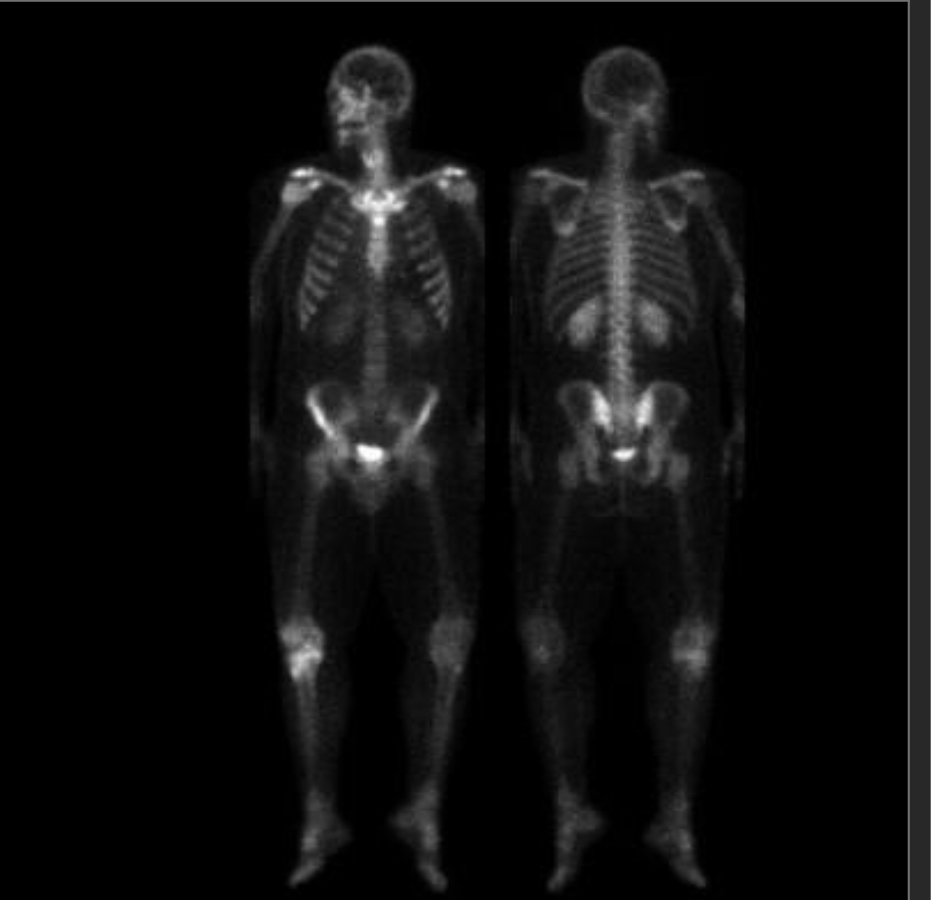

21M without trauma

Osteosarcoma.

with MR to help we see soft tissue extension and cortical breakthrough

Ewing and other small round blue cell tumors are also in diffx (or smoldering infx) but less likely based on age